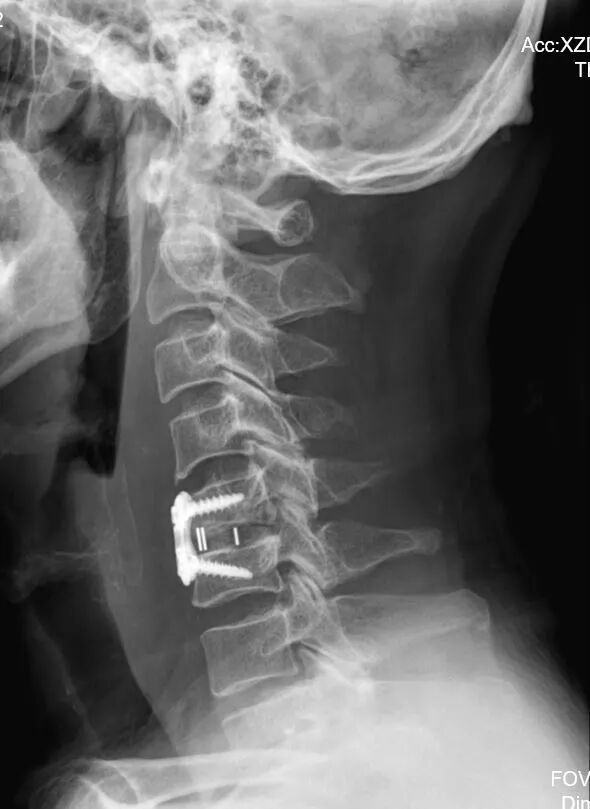

颈前路髓核摘除椎管减压、椎间植骨融合内固定术

仅耗时2小时,出血量20ml

顺利完成手术,主打一个微创高效

术后恢复更是“开挂”

第三天,李先生就能下床正常行走

上肢麻木胀痛大幅缓解

走路的“踩云感”彻底消失

腿部有劲、身体超稳